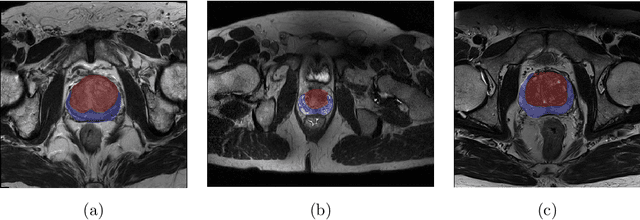

Abstract:Prostate cancer is the most common malignant tumors in men but prostate Magnetic Resonance Imaging (MRI) analysis remains challenging. Besides whole prostate gland segmentation, the capability to differentiate between the blurry boundary of the Central Gland (CG) and Peripheral Zone (PZ) can lead to differential diagnosis, since tumor's frequency and severity differ in these regions. To tackle the prostate zonal segmentation task, we propose a novel Convolutional Neural Network (CNN), called USE-Net, which incorporates Squeeze-and-Excitation (SE) blocks into U-Net. Especially, the SE blocks are added after every Encoder (Enc USE-Net) or Encoder-Decoder block (Enc-Dec USE-Net). This study evaluates the generalization ability of CNN-based architectures on three T2-weighted MRI datasets, each one consisting of a different number of patients and heterogeneous image characteristics, collected by different institutions. The following mixed scheme is used for training/testing: (i) training on either each individual dataset or multiple prostate MRI datasets and (ii) testing on all three datasets with all possible training/testing combinations. USE-Net is compared against three state-of-the-art CNN-based architectures (i.e., U-Net, pix2pix, and Mixed-Scale Dense Network), along with a semi-automatic continuous max-flow model. The results show that training on the union of the datasets generally outperforms training on each dataset separately, allowing for both intra-/cross-dataset generalization. Enc USE-Net shows good overall generalization under any training condition, while Enc-Dec USE-Net remarkably outperforms the other methods when trained on all datasets. These findings reveal that the SE blocks' adaptive feature recalibration provides excellent cross-dataset generalization when testing is performed on samples of the datasets used during training.